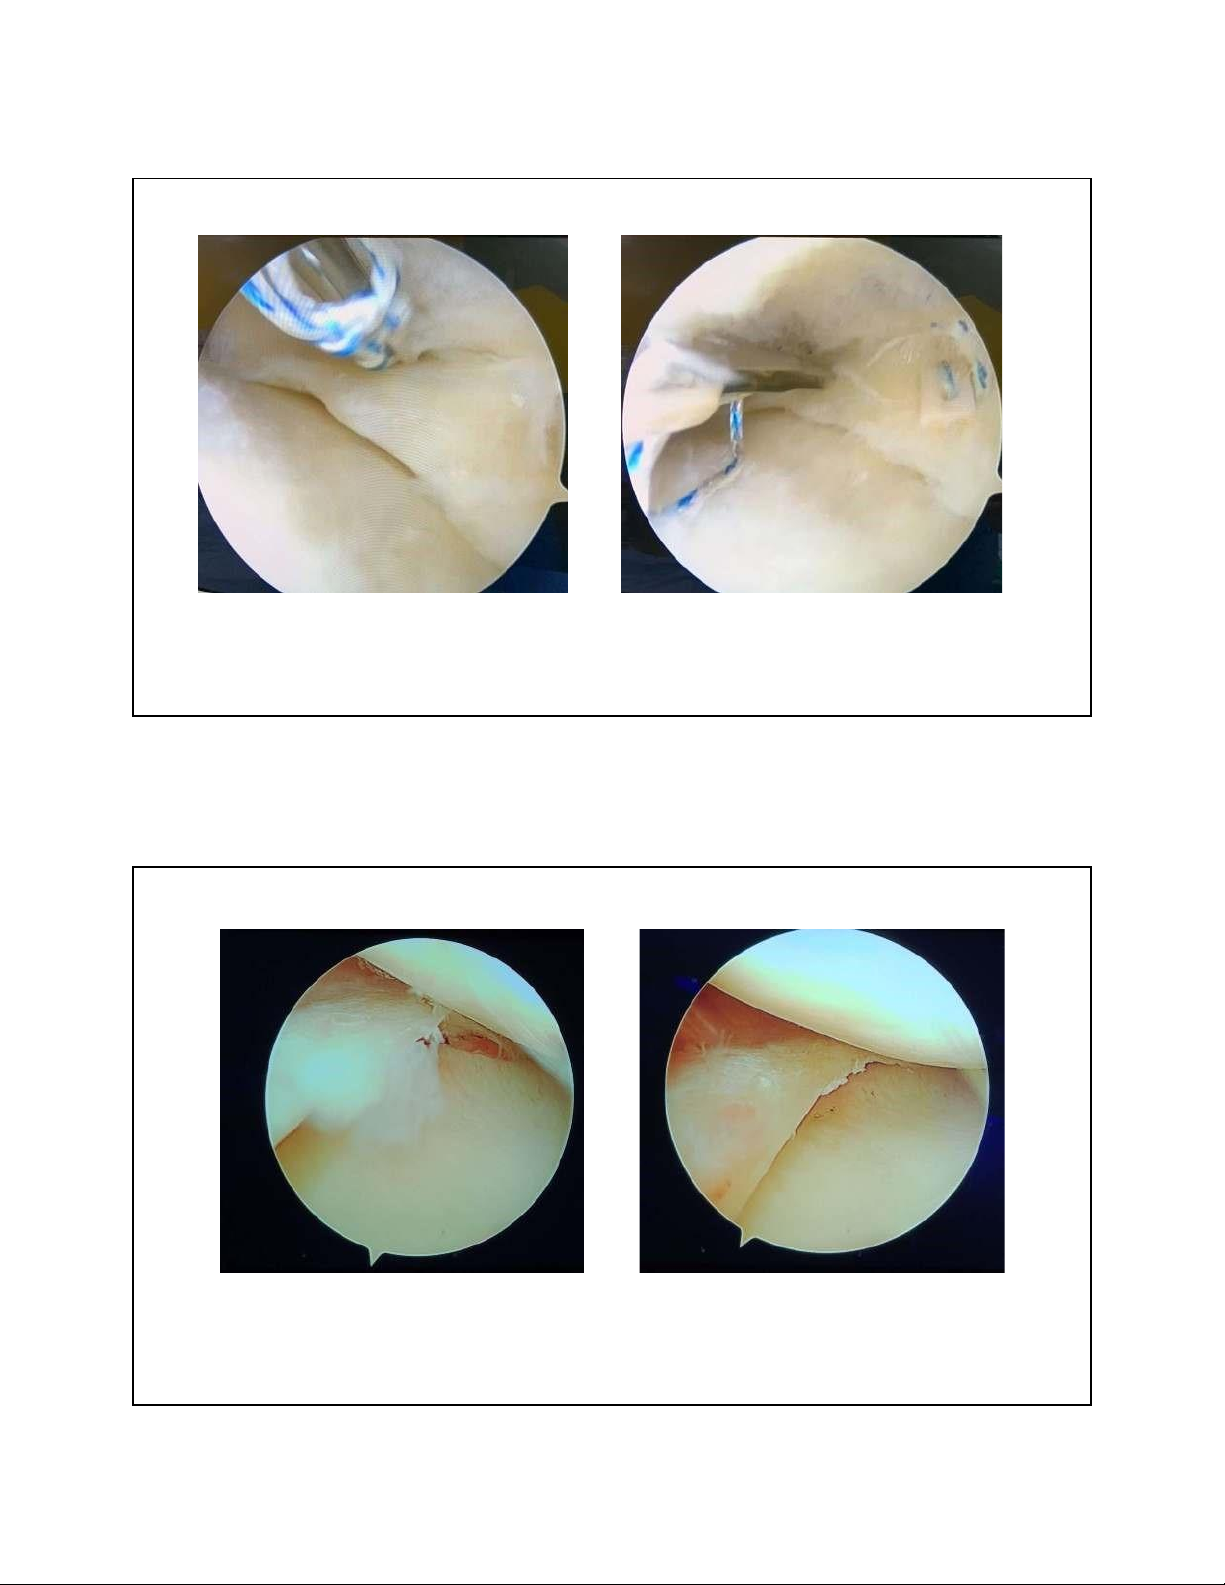

2. RÁCH SỤN CHÊM – ĐIỀU TRỊ

• PT nội soi khâu sụn chêm giúp

bảo toàn giải phẫu, hạn chế nguy cơ thoái hóa khớp

• Cắt lọc bỏ phần rách khi rách

phần trắng, rách thoái hóa gia tăng nguy cơ thoái hóa khớp. 8 lOMoAR cPSD| 22014077 7/15/2023

2. RÁCH SỤN CHÊM – KHÂU SỤN CHÊM 9

2. RÁCH SỤN CHÊM – CẮT LỌC SỤN CHÊM 10 lOMoAR cPSD| 22014077 7/15/2023 3. TỔN THƯƠNG DÂY CHẰNG